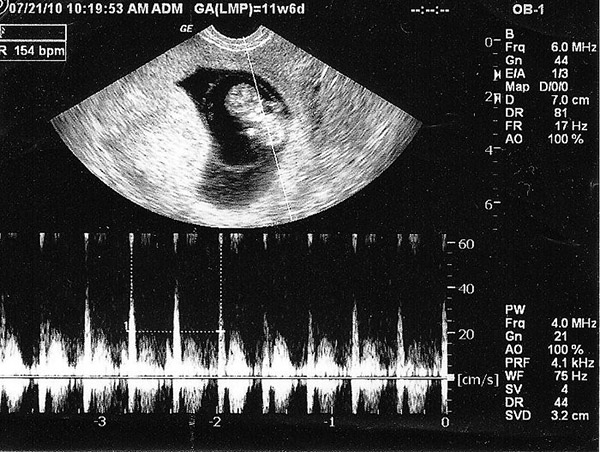

Tuỳ vào tốc độ phát triển của thai nhi mà nhiều bé vào tuần thứ 6 đã có tim thai, nhiều cháu chưa. Tim thai đã được dần hoàn thiện từ tuần thứ 4 nhưng đến tuần 6, nhịp tim của bé đã đập khoảng 120 – 160 lần/ phút. Tốc độ này gấp đôi người lớn bình thường.

Bên cạnh đấy, nhiều thai nhi sẽ có tim thai ở tuần thứ 7 và tới tuần 12 là quá rõ ràng rồi. Nguyên nhân có thể do tính tuổi sai bị lệch hoặc thời điểm rụng trứng có thể bị muộn so với chu kỳ cuối. Thực chất không làm sao cả, vì cái này cũng có thể do yếu tố di truyền.

Nếu muốn biết chắc thai nhi có tim thai bình thường hay không thì mẹ xem vào khoảng tuần 8 là tốt nhất.